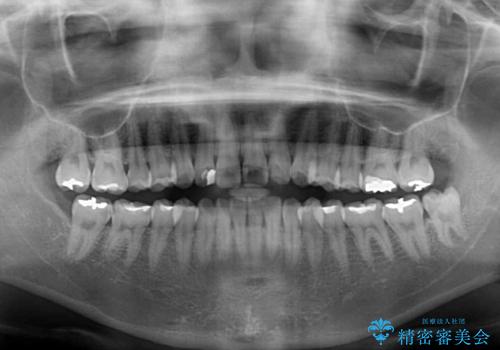

インビザライン適用の歯列であったため、歯と歯の間を削るIPRを用いて改善することとしました。

お仕事柄、長時間のマウスピース装着が苦ではなかったので、歯列はすぐに整いましたが、ゆっくりとした交換頻度であったので、2年ほどの治療期間を要しました。